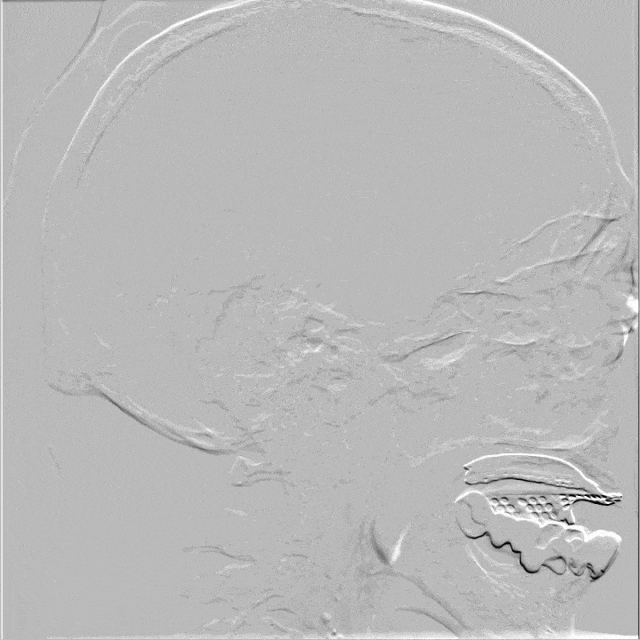

术前造影

术前右侧颈总动脉造影示颈内动脉起始段次全闭塞